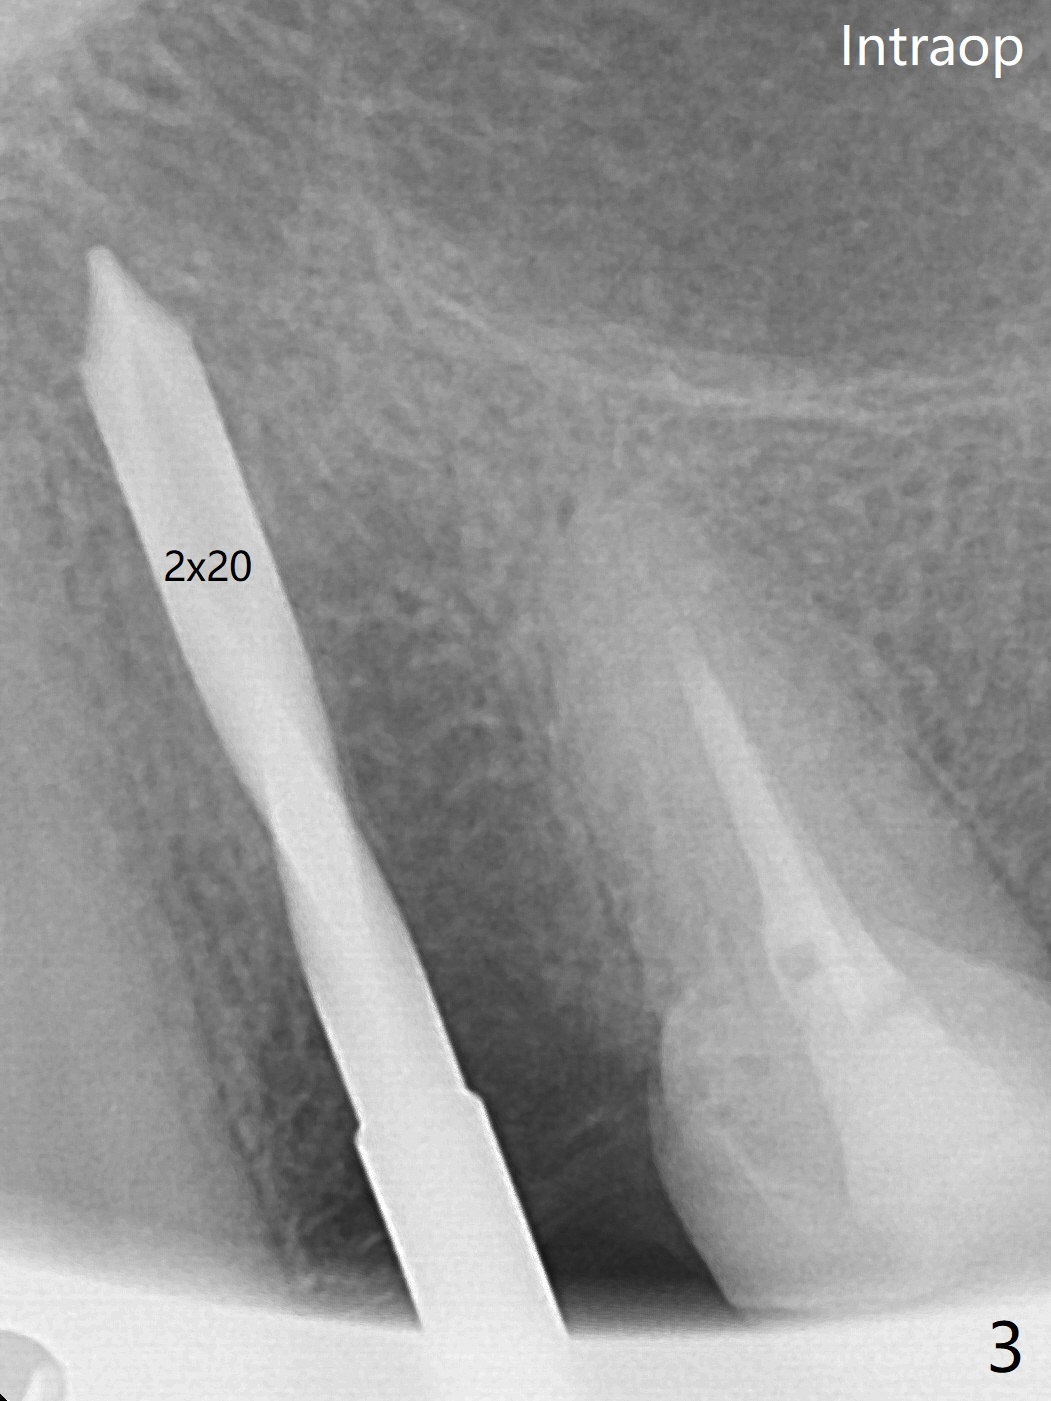

一个月前12号牙仅有隐裂(与术前即刻(图一)对比),当时CT显示轻度颊侧根尖缺损(图二:>)。拔牙后颊侧根尖没有骨板,所以钻洞偏腭侧(图三);完成最后钻头(3毫米)后,后者保持原位,先在颊侧根尖植骨,然后取出钻头,植入植体(图四),放置基台后,在后两者周围再置入骨粉,最后制作临时牙冠固定骨粉。由于骨质密度低(图二;术中钻洞容易),选择20毫米植体,扭力50Ncm。